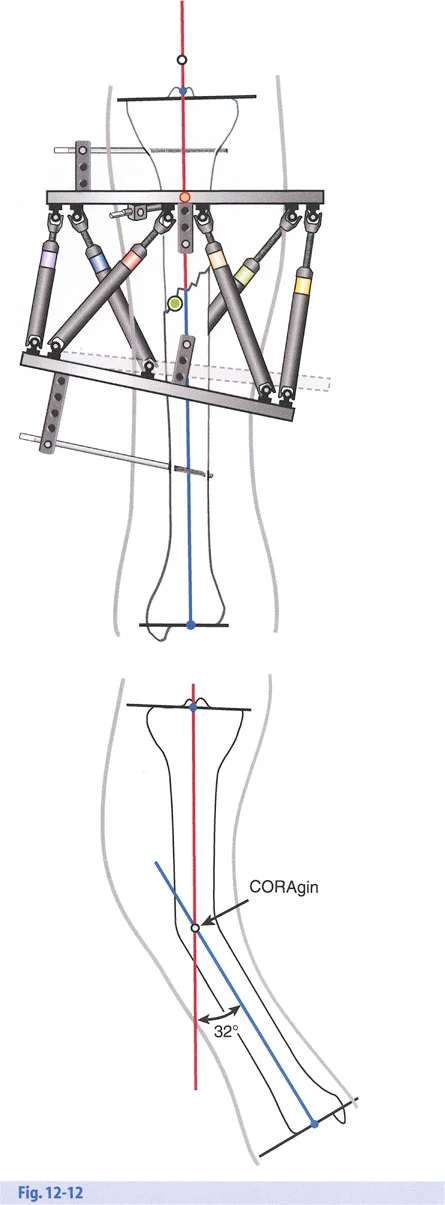

- الأشعة السينية الطويلة للطرفين (Long-leg Standing X-rays): هذه الأشعة ضرورية لتقييم المحور الميكانيكي للطرف بالكامل أثناء الوقوف. تسمح بتحديد مركز دوران الانحراف (CORA) بدقة، وهو النقطة التي يجب أن تتمحور حولها عملية التصحيح.

تحدي مركز دوران الانحراف (CORA) القريب من المفصل

لمطابقة مفصلة المثبت الخارجي مع المستوى الدقيق لمركز دوران الانحراف (CORA)، يجب غالبًا بناء المفصلة فوق أو تحت مستوى الحلقة الفعلية. يُعرف هذا في مبادئ بالي باسم تجميع المفصلة القريبة من المفصل (juxta-articular hinge assembly).

إذا كان مركز دوران الانحراف (CORA) يقع بالقرب من خط المفصل، فإن وضع حلقة إليزاروف القياسية عند هذا المستوى بالضبط مستحيل دون انتهاك مساحة المفصل أو شد الهياكل الكبسولية الحيوية. لذلك، يتم تثبيت الحلقة المرجعية بالعظم الكثيف أو العظم الطويل المتاح، ويتم بناء آلية المفصلة باستخدام قضبان ملولبة، ولوحات توصيل، ودعامات. ثم يتم "إنزالها" (أو رفعها) لتتطابق تمامًا مع مركز دوران الانحراف (CORA) الهندسي الحقيقي.

قواعد بالي لقطع العظم (Osteotomy Rules) في وضع الأجهزة

فهم قواعد بالي لقطع العظم أمر لا غنى عنه لتخطيط الإطار:

- قاعدة قطع العظم 1: عندما يمر قطع العظم ومحور تصحيح الانحراف (ACA) كلاهما عبر مركز دوران الانحراف (CORA)، فإن نهايات العظم ستنحرف دون ترجمة (انزياح). يتم استعادة المحور الميكانيكي، وتظل نهايات العظم متقاربة تمامًا، مما يخلق تصحيحًا كلاسيكيًا "إسفينيًا مفتوحًا" أو "إسفينيًا مغلقًا".

- قاعدة قطع العظم 2: عندما يمر محور تصحيح الانحراف (ACA) عبر مركز دوران الانحراف (CORA)، ولكن يتم إجراء قطع العظم على مستوى مختلف (غالبًا بسبب ضعف جودة العظم عند CORA أو مشاكل في الجلد)، فإن نهايات العظم ستنحرف وتخضع لترجمة محسوبة ومقصودة لإعادة محاذاة المحور الميكانيكي.

- قاعدة قطع العظم 3: (للاكمال) عندما يمر قطع العظم عبر مركز دوران الانحراف (CORA)، ولكن يتم وضع محور تصحيح الانحراف (ACA) خارج CORA، سيتم إنشاء تشوه ترجمة جديد، وهو خطأ شائع في وضع المفصلات غير المخطط له جيدًا.

في المنشآت القريبة من المفصل، غالبًا ما نعتمد على قاعدة قطع العظم 2. نظرًا لأنه لا يمكننا قطع العظم بأمان عند خط المفصل تمامًا (مركز دوران الانحراف CORA)، فإننا نقطع العظم في مستوى أدنى في منطقة الميتافيسيس. بعد تحقيق التصحيح الزاوي عبر المفصلات (محور تصحيح الانحراف ACA)، يتم إعادة محاذاة خطوط المحور الميكانيكي بشكل مثالي، ولكن نهايات العظم في موقع قطع العظم تتحرك بالنسبة لبعضها البعض.